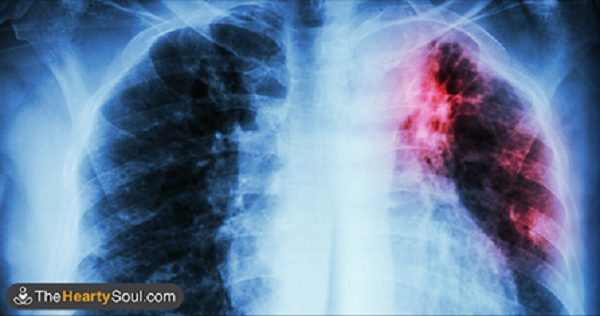

Курение может вызвать различные заболевания, в том числе сахарный диабет, инсульт, рак, сердечно-сосудистые заболевания, заболевания легких, таких как эмфизема и хронический бронхит.

Это может значительно повысить риск глазных заболеваний, туберкулеза, а также вопросы иммунной системы, такие как ревматоидный артрит. Кроме того, это приводит к эректильной дисфункции у мужчин.

Поэтому, будучи в состоянии очистить легкие и устранить все токсины означает, что вы можете предотвратить все эти серьезные проблемы со здоровьем, независимо от того, вы курильщик или некурящий.